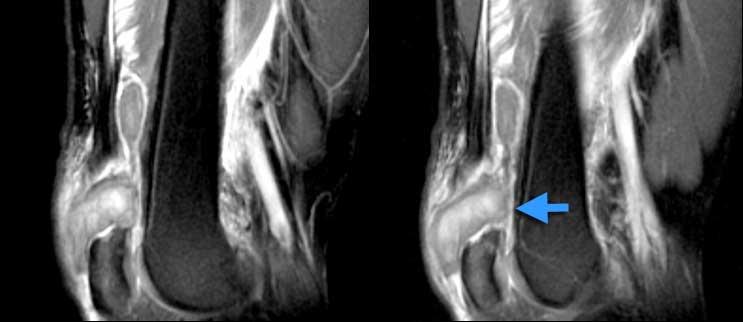

TRÁI: Rách một phần gân cơ tứ đầu đùi. Chỉ có gân cơ thẳng đùi bị rách (mũi tên xanh). PHẢI: Bệnh lý gân có từ trước (vòng tròn vàng) trên ảnh mặt phẳng ngang.

Một ví dụ khác về rách một phần gân cơ tứ đầu đùi.

Rách hoàn toàn gân cơ tứ đầu đùi. Ảnh chuỗi xung T2W mặt phẳng đứng dọc. Mất liên tục hoàn toàn. Khối máu tụ ở giữa.

Khi không còn sự liên tục giữa xương bánh chè và gân cơ tứ đầu đùi, đó là rách hoàn toàn.